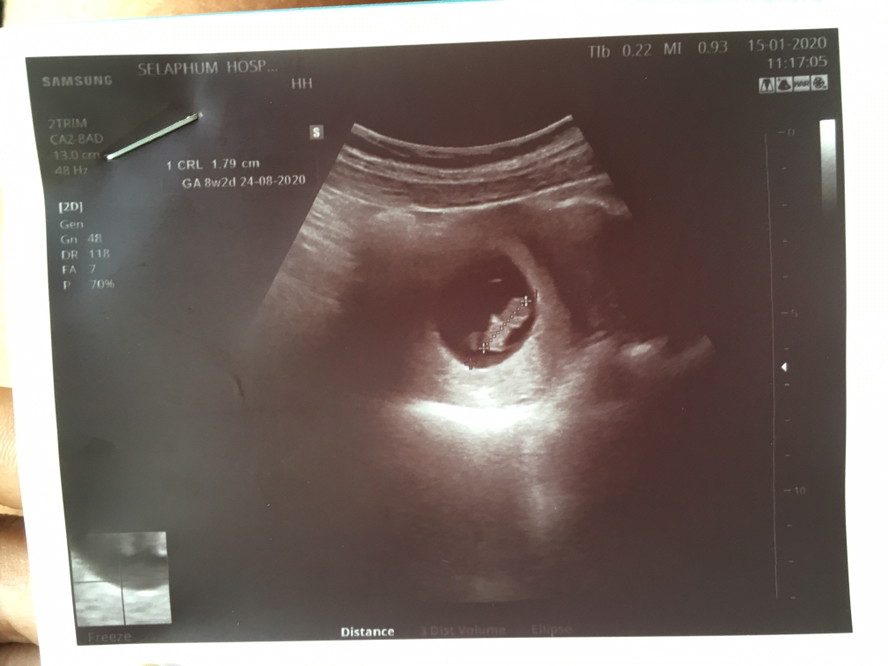

บ้านนี้ 8week ตัวเล็กไปมั้ยค่ะ☺️

ซาวตอน8w2d ทีมสิงหาจ้า